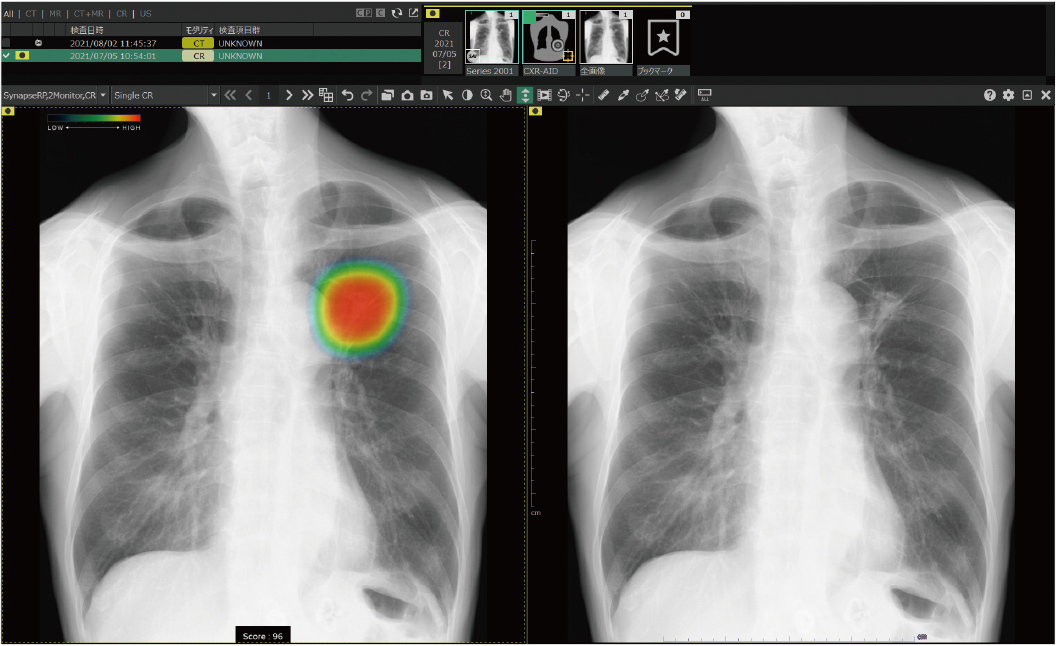

胸部X線画像病変検出ソフトウェア CXR-AID導入のお知らせ

当院では、令和5年3月10日よりAI技術を活用して胸部単純X線画像から結節・腫瘤影、浸潤影、気胸の3つの画像所見を検出し医師の画像診断を支援する「胸部X線画像病変検出ソフトウェア(CXR-AID)」の運用を開始いたしました。

AI技術を活用し、撮影した胸部単純X線画像をAIが自動解析、結節・腫瘤影、浸潤影、気胸が疑われる領域を検出・マーキングします。その領域を医師が再確認することで、診断の精度向上が期待できます。